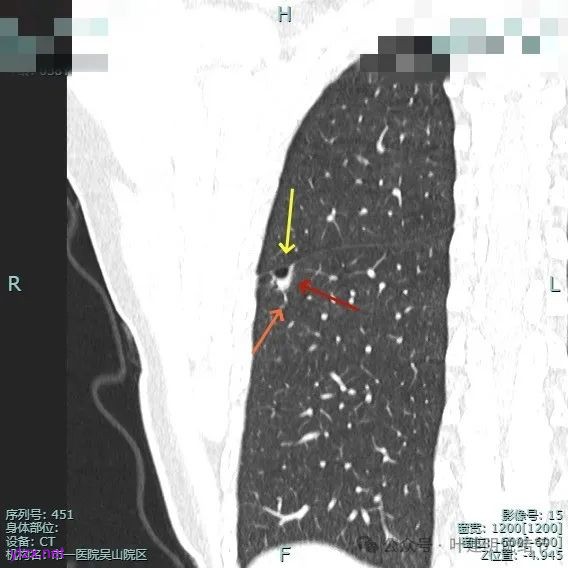

病灶部分囊壁是混合磨玻璃成分的,整体轮廓较清。

边缘区也有偏实性成分,磨玻璃成分也还是明显的,有微小血管进入。

靶重建的影像上看,病灶的囊壁明显厚薄不均,有小血管进入,一侧的边似就是斜裂的样子。

囊壁有磨玻璃成分,边缘毛糙,有少许偏实性成分,仍有磨玻璃成分。

血管走向病灶,囊壁略不均。